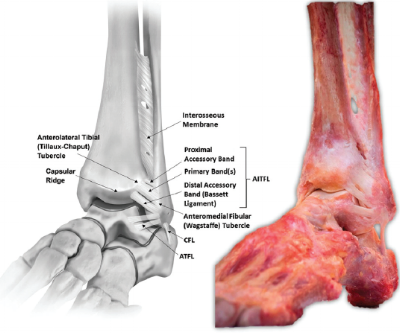

Ankle syndesmosis ligaments

Most report pain and point tenderness over the AITFL and/or PITFL.

Tenderness can extend superiorly into interossesous membrane.